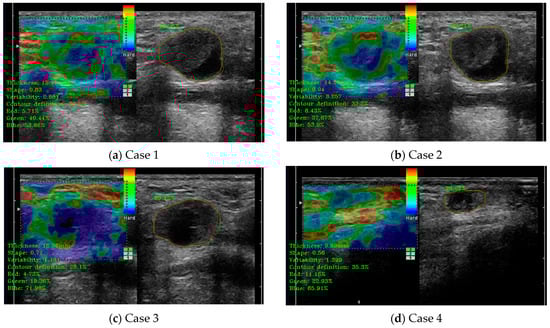

3.3. Doppler Analysis Module Performance Evaluation

In this case, the medical indicators for B-mode US evaluation that were also valid for Doppler-mode US were kept. Besides those, some specific indicators and algorithms were developed. The specific Doppler ultrasound indicators evaluated some extra parameters, such as the vascularity ratio and the vascularity position presented in Figure 8. On the left side of the images are printed, in a green color, the numerical results of several indicators, including the vascularity ratio, in the percentages named “Color”. As can be seen for all the cases presented in Figure 8, the percentages are below the defined cut-off threshold for metastasis indication.

Figure 8.

(a–d) illustrate cases of lymph node (LN) automatic detection using Doppler-mode ultrasound (US), incorporating shape parameter evaluation and Doppler US indicator assessment for enhanced accuracy. The red contour represents the manually delineated region by the doctor, while the green contour corresponds to the system’s automatically detected boundary. The percentage value indicates the detection accuracy.